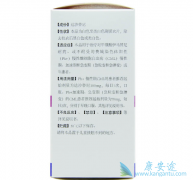

施达赛 (达沙替尼),在扩大适应症方面取得了新进展,有研究表明,该药物具有治疗卵巢癌的潜力。来自英国肿瘤研究所的研究者将施达赛(达沙替尼)用于具有BRCA1突变的卵巢癌小鼠模型,发现施达赛(达沙替尼)能够阻止肿瘤细胞的增殖。BRCA1是女性罹患 ...

施达赛 是由美国百时美-施贵宝公司(Bristol-Myers Squibb)开发研制的,是第二代信号传导抑制剂。此药在结构上不同于伊马替尼,它以活化的构型结合到abl,不但可抑制abl激酶,还可抑制Src家族激酶。除了T315I以外的已知基因突变类型都有抑制作用,其抑制 ...

通常情况下,经酪氨酸激酶抑制剂(TKI) 施达赛 治疗后的慢性髓系白血病(CML)患者会发生淋巴细胞增多症。众所周知,施达赛具有免疫抑制作用,但也很有可能会抑制淋巴细胞增生。研究作者Charles A. Schiffer博士说,奇怪的是,在一些小型研究中,患者经 ...

慢性髓性白血病(CML)是造血干细胞的恶性骨髓增殖性疾病,目前酪氨酸激酶抑制剂(TKI)是该病慢性期患者的主要治疗选择。 施达赛 作为第二代TKI的代表药物已被批准用于CML的一线和二线治疗。在施达赛一线治疗新诊断CML-CP患者的重要研究中,DASISION研 ...

施达赛 (Dasatinib)是一种针对BCR-ABL基因和SRC基因变异的第二代酪氨酸激酶抑制剂(TKI),其片剂配方现已被批准用于儿童慢性粒细胞白血病慢性期(CML-CP)治疗。但是,施达赛对于儿童CML-CP的疗效及安全性究竟如何呢?一项针对儿童CML-CP的迄今为止 ...